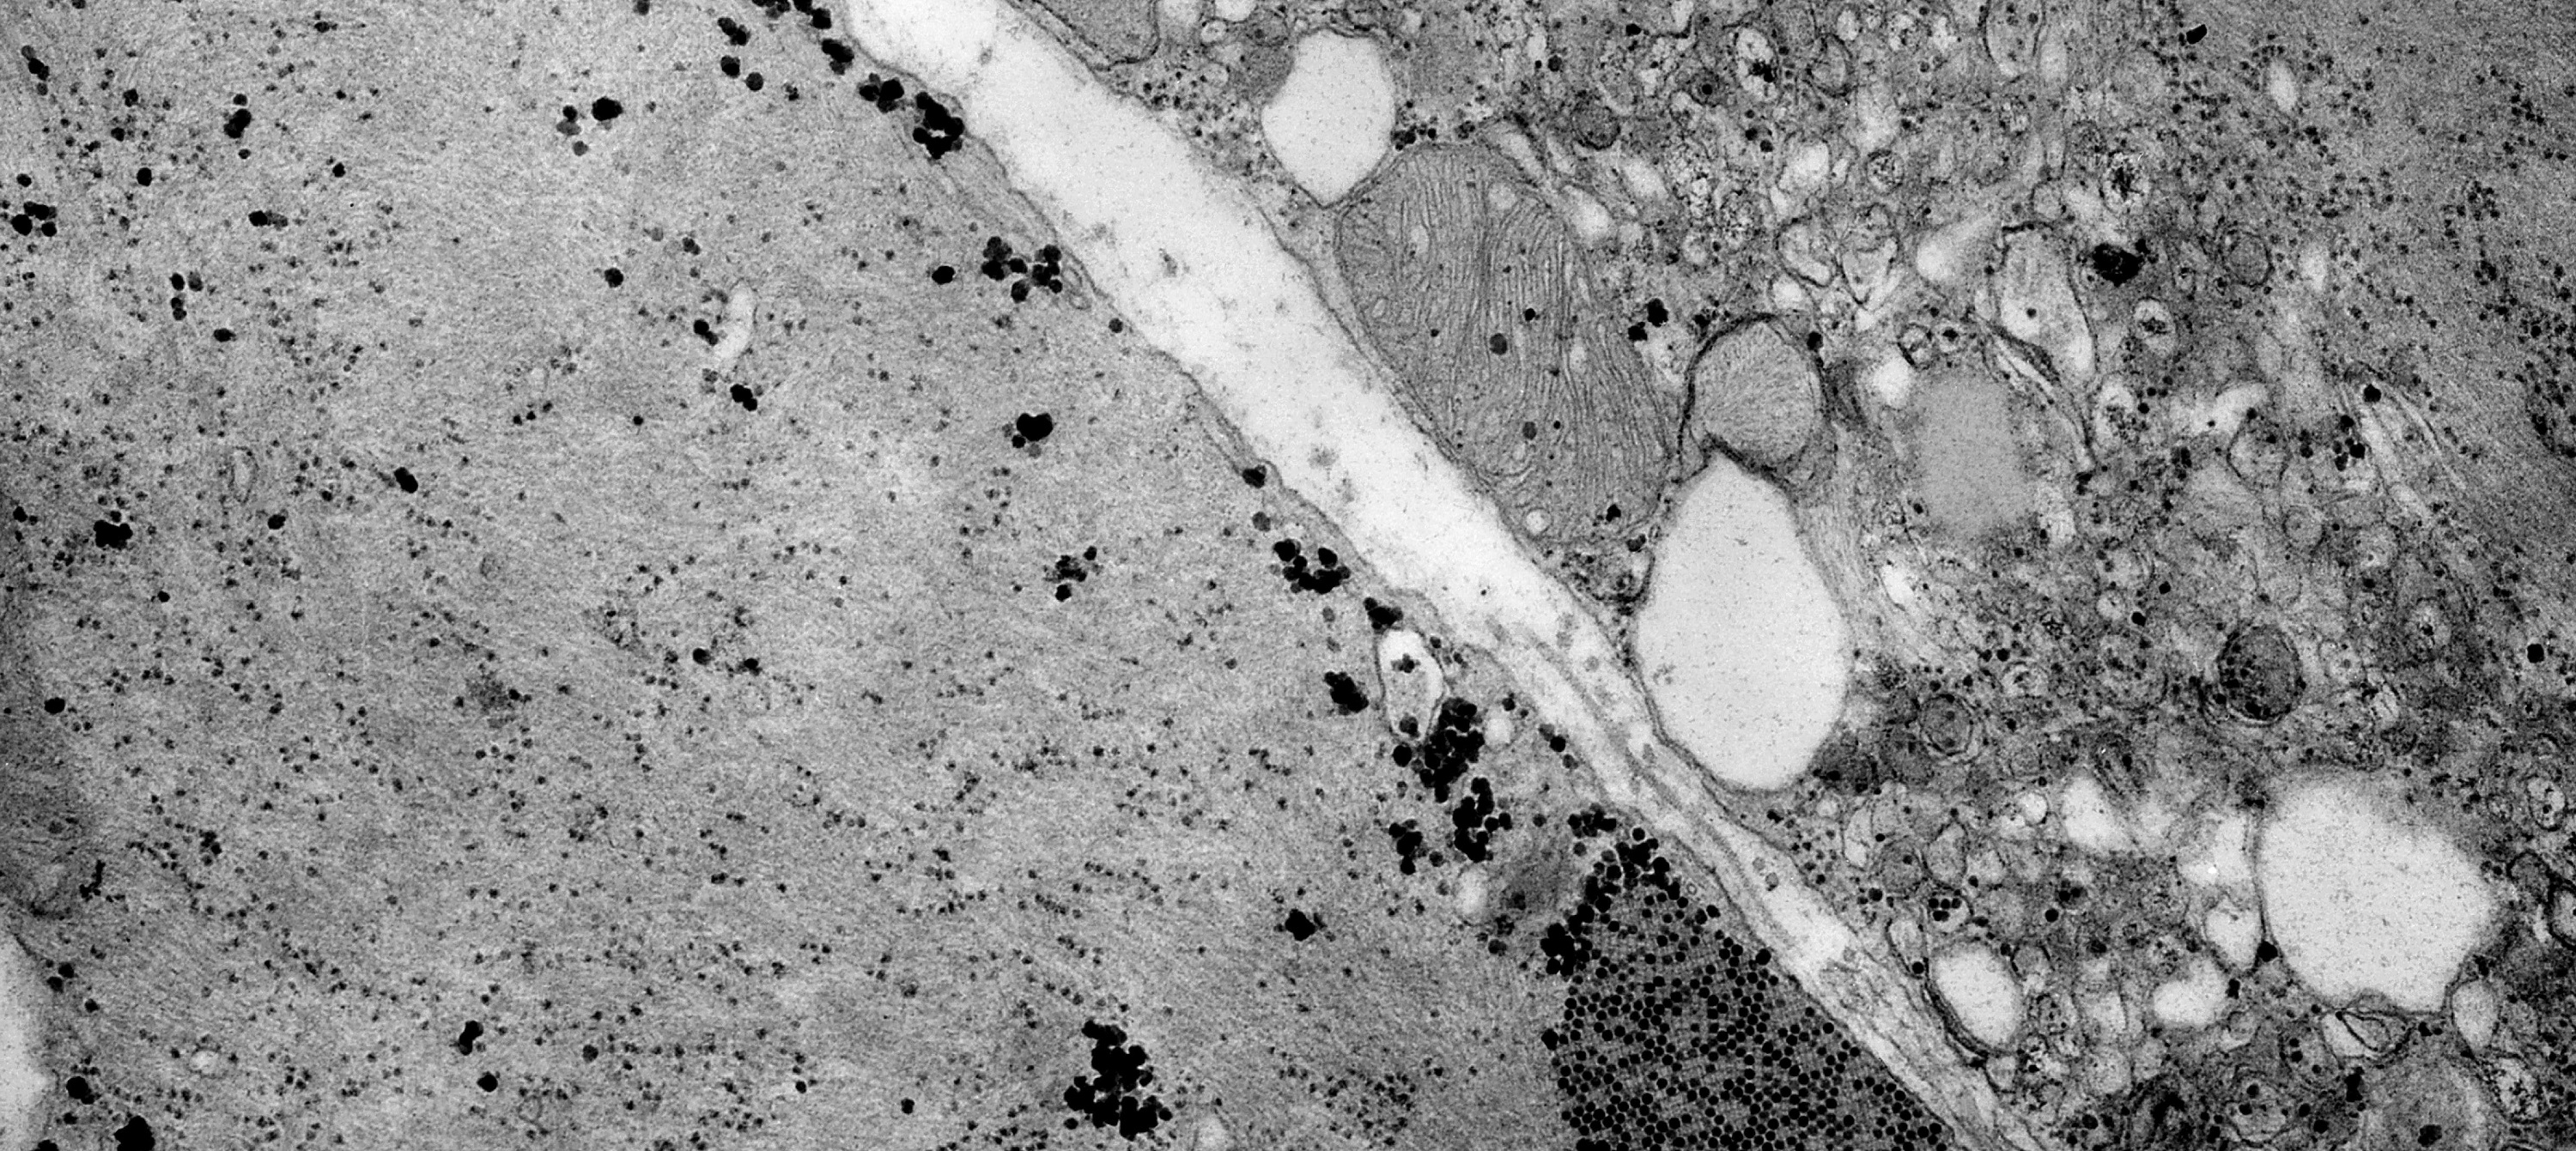

• CIBERER

Proponen prevenir el daño oxidativo mitocondrial como diana terapéutica de la enfermedad de Charcot-Marie-Tooth

21/07/2021